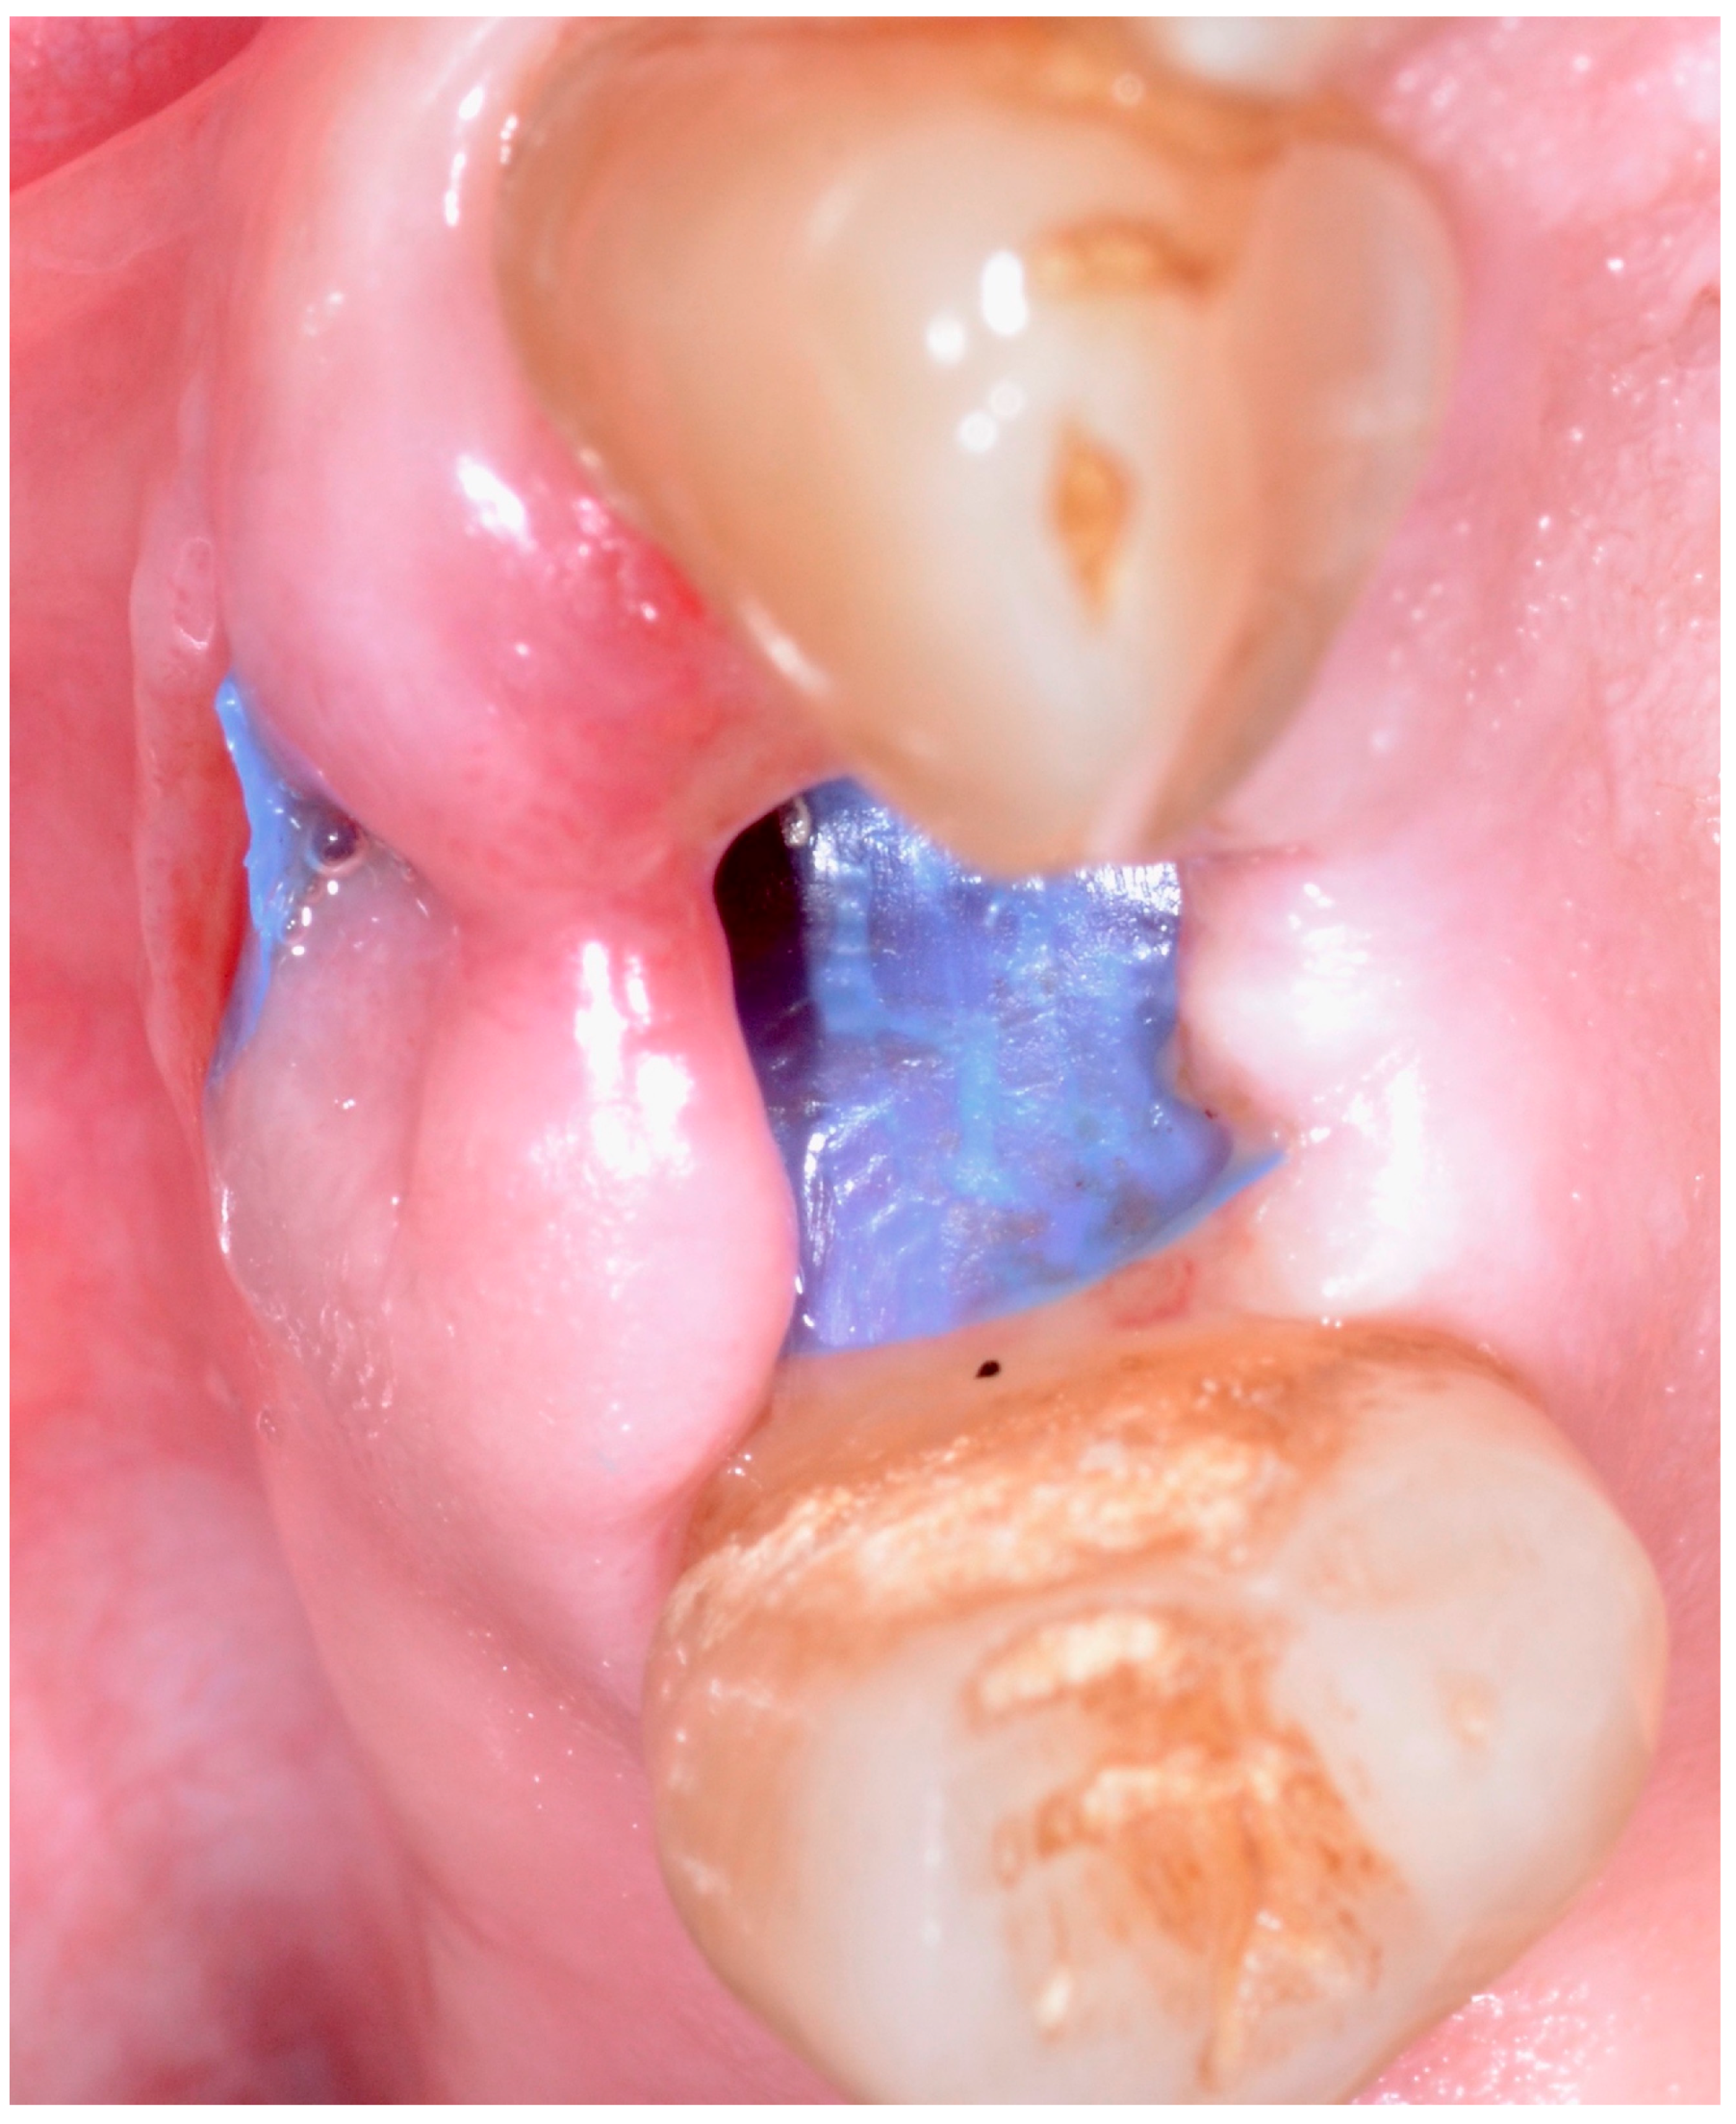

5.4. Surgical Technique